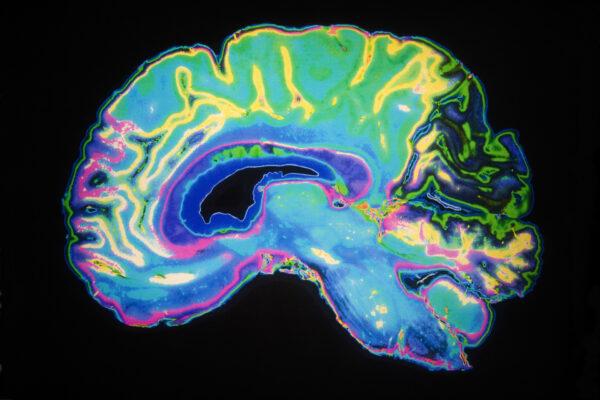

A colorful image of a human brain is seen as part of a report released by a UCLA-led team of scientists that reveals why sleep is vital to health and healing. (Courtesy of UCLA/Daisy Daisy/Shutterstock)